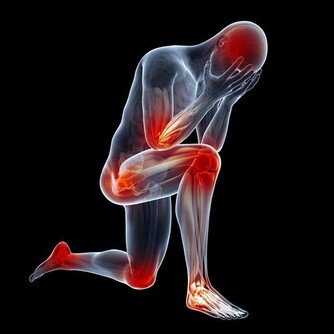

三、肩周炎有哪些表現及如何診斷?1.肩部疼痛:病初肩部呈陣發性疼痛,多數為慢性發作,以後疼痛逐漸加劇或頓痛,或刀割樣痛,且呈持續性,氣候變化或勞累後加重,疼痛可向頸項及上肢放射(此時須與頸椎病鑑別),肩痛晝輕夜重為其特點。

2.肩關節活動受限:肩關節向各方向活動均可受限,以外展、上舉、內外旋更為明顯,特別是梳頭、穿衣、洗臉、叉腰等動作均難以完成。

3.怕冷:患肩怕冷,不少患者終年用棉墊包肩,即使在暑天,肩部也不敢吹風。

4.壓痛:多數患者在肩關節周圍可觸到明顯的壓痛點。

5.肌肉痙攣與萎縮:三角肌、岡上肌等肩周圍肌肉早期可出現痙攣,晚期可發生廢用性肌萎縮,此時疼痛症狀反而減輕。